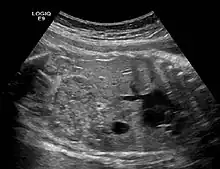

![]() | |

| Ectopic crossed fused kidney in a fetus approx. 34 weeks | |